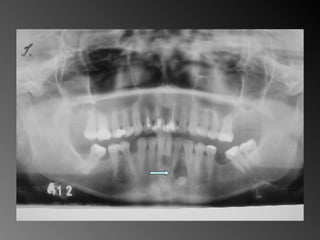

Granuloma (Lesão) Periférico de Células Gigantes A excisão cirúrgica deve ser antecedida de exame radiográfico, pois lesão não completamente removida e/ou com infiltração óssea, pode recorrer

Granuloma (Lesão) Periféricode Células Gigantes A excisão cirúrgica deve ser antecedida de exame radiográfico, pois lesão não completamente removida e/ou com infiltração óssea, pode recorrer

26 - Pacientedo sexo feminino, 30 anos de idade, se apresentou com aumento de volume no corpo da mandíbula, região dos dentes 45, 46 e 47, assintomático e com evolução de aproximadamente 1 ano. Pelo exame clínico constatamos expansão óssea e deslocamento dos dentes 45 e 46 de suas posições normais. Através de radiografia panorâmica observamos uma imagem radiográfica multilocular onde as trabéculas ósseas se encontravam perpendicularmente umas às outras e em outras regiões com aspecto de bolha de sabão. Com base no quadro clínico, o diagnóstico é: a) Ceratocisto e mixoma odontogênico. b) Odontoma composto e ameloblastoma. c) Mixoma odontogênico e ameloblastoma. d) Mixoma odontogênico e odontoma composto. e) Ameloblastoma e ceratocisto.

Mixoma Freqüência: -Segunda e terceira década de vida -Atinge pouco mais a maxila que a mandíbula (região posterior + frequente)

Exame complementares RadiografiaPanorâmica; Radiografia Oculsal; Teste de Vitalidade; Punção Exploratória; Biópsia incisional.

Teste de VitalidadeDente 43: Negativo Dentes 42,44 e 45: Positivo.